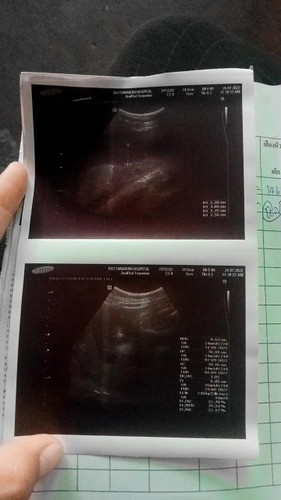

น้ำหนักลูก

ลูกสาวบ้านนี้35วีค น้ำหนัก2450g บ้านอื่นน้ำหนักเท่าไรกันบ้าง